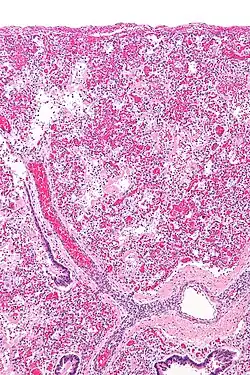

ARDS is a form of fluid accumulation in the lungs not explained by heart failure (noncardiogenic pulmonary edema). It is typically provoked by an acute injury to the lungs that results in flooding of the lungs' microscopic air sacs responsible for the exchange of gases such as oxygen and carbon dioxide with capillaries in the lungs.[13] Additional common findings in ARDS include partial collapse of the alveoli (atelectasis) and low levels of oxygen in the blood (hypoxemia). The clinical syndrome is associated with pathological findings including pneumonia, eosinophilic pneumonia, cryptogenic organizing pneumonia, acute fibrinous organizing pneumonia, and diffuse alveolar damage (DAD). Of these, the pathology most commonly associated with ARDS is DAD, which is characterized by a diffuse inflammation of lung tissue. The triggering insult to the tissue usually results in an initial release of chemical signals and other inflammatory mediators secreted by local epithelial and endothelial cells.

Neutrophils and some T-lymphocytes quickly migrate into the inflamed lung tissue and contribute in the amplification of the phenomenon. The typical histological presentation involves diffuse alveolar damage and hyaline membrane formation in alveolar walls. Although the triggering mechanisms are not completely understood, recent research has examined the role of inflammation and mechanical stress.